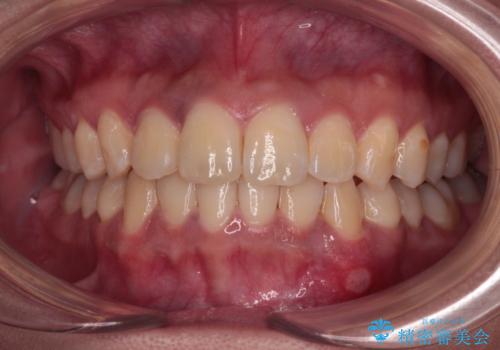

前歯のデコボコと隠れてしまう下顎前歯 インビザラインですっきりと改善

- 11ヶ月

インビザライン発注後に長期滞在先から2年間ほど帰国することができず、インビザラインの有効期限内に終了できるのか不安でしたが、矯正治療開始後は十分な装着時間を達成され、1年未満の期間で無事に終えることができました。